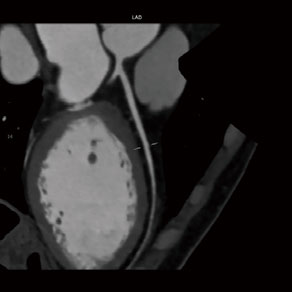

CT冠状动脉成像图

CT冠状动脉造影(CTA)是经静脉注射造影剂后利用螺旋CT扫描再经过计算机处理重建得出的心脏冠状动脉成像的一种检查方法,能够清楚的呈现冠状动脉形态,诊断有无狭窄改变。这种技术是从手臂静脉输入对比剂,就象平时输液是一样,因此几乎没有创伤性,非常安全。与DSA冠状动脉造影相比较,因为不用插管,所用时间也短。

1、怀疑冠心病。常感胸闷、胸痛、心前区不适等,判断其冠状动脉形态,有无狭窄及狭窄程度。

3、冠状动脉介入治疗和手术搭桥术后定期复查。包括冠状动脉搭桥术后及冠状动脉支架置入术后,观察其是否通畅或者是否存在再狭窄等情况;